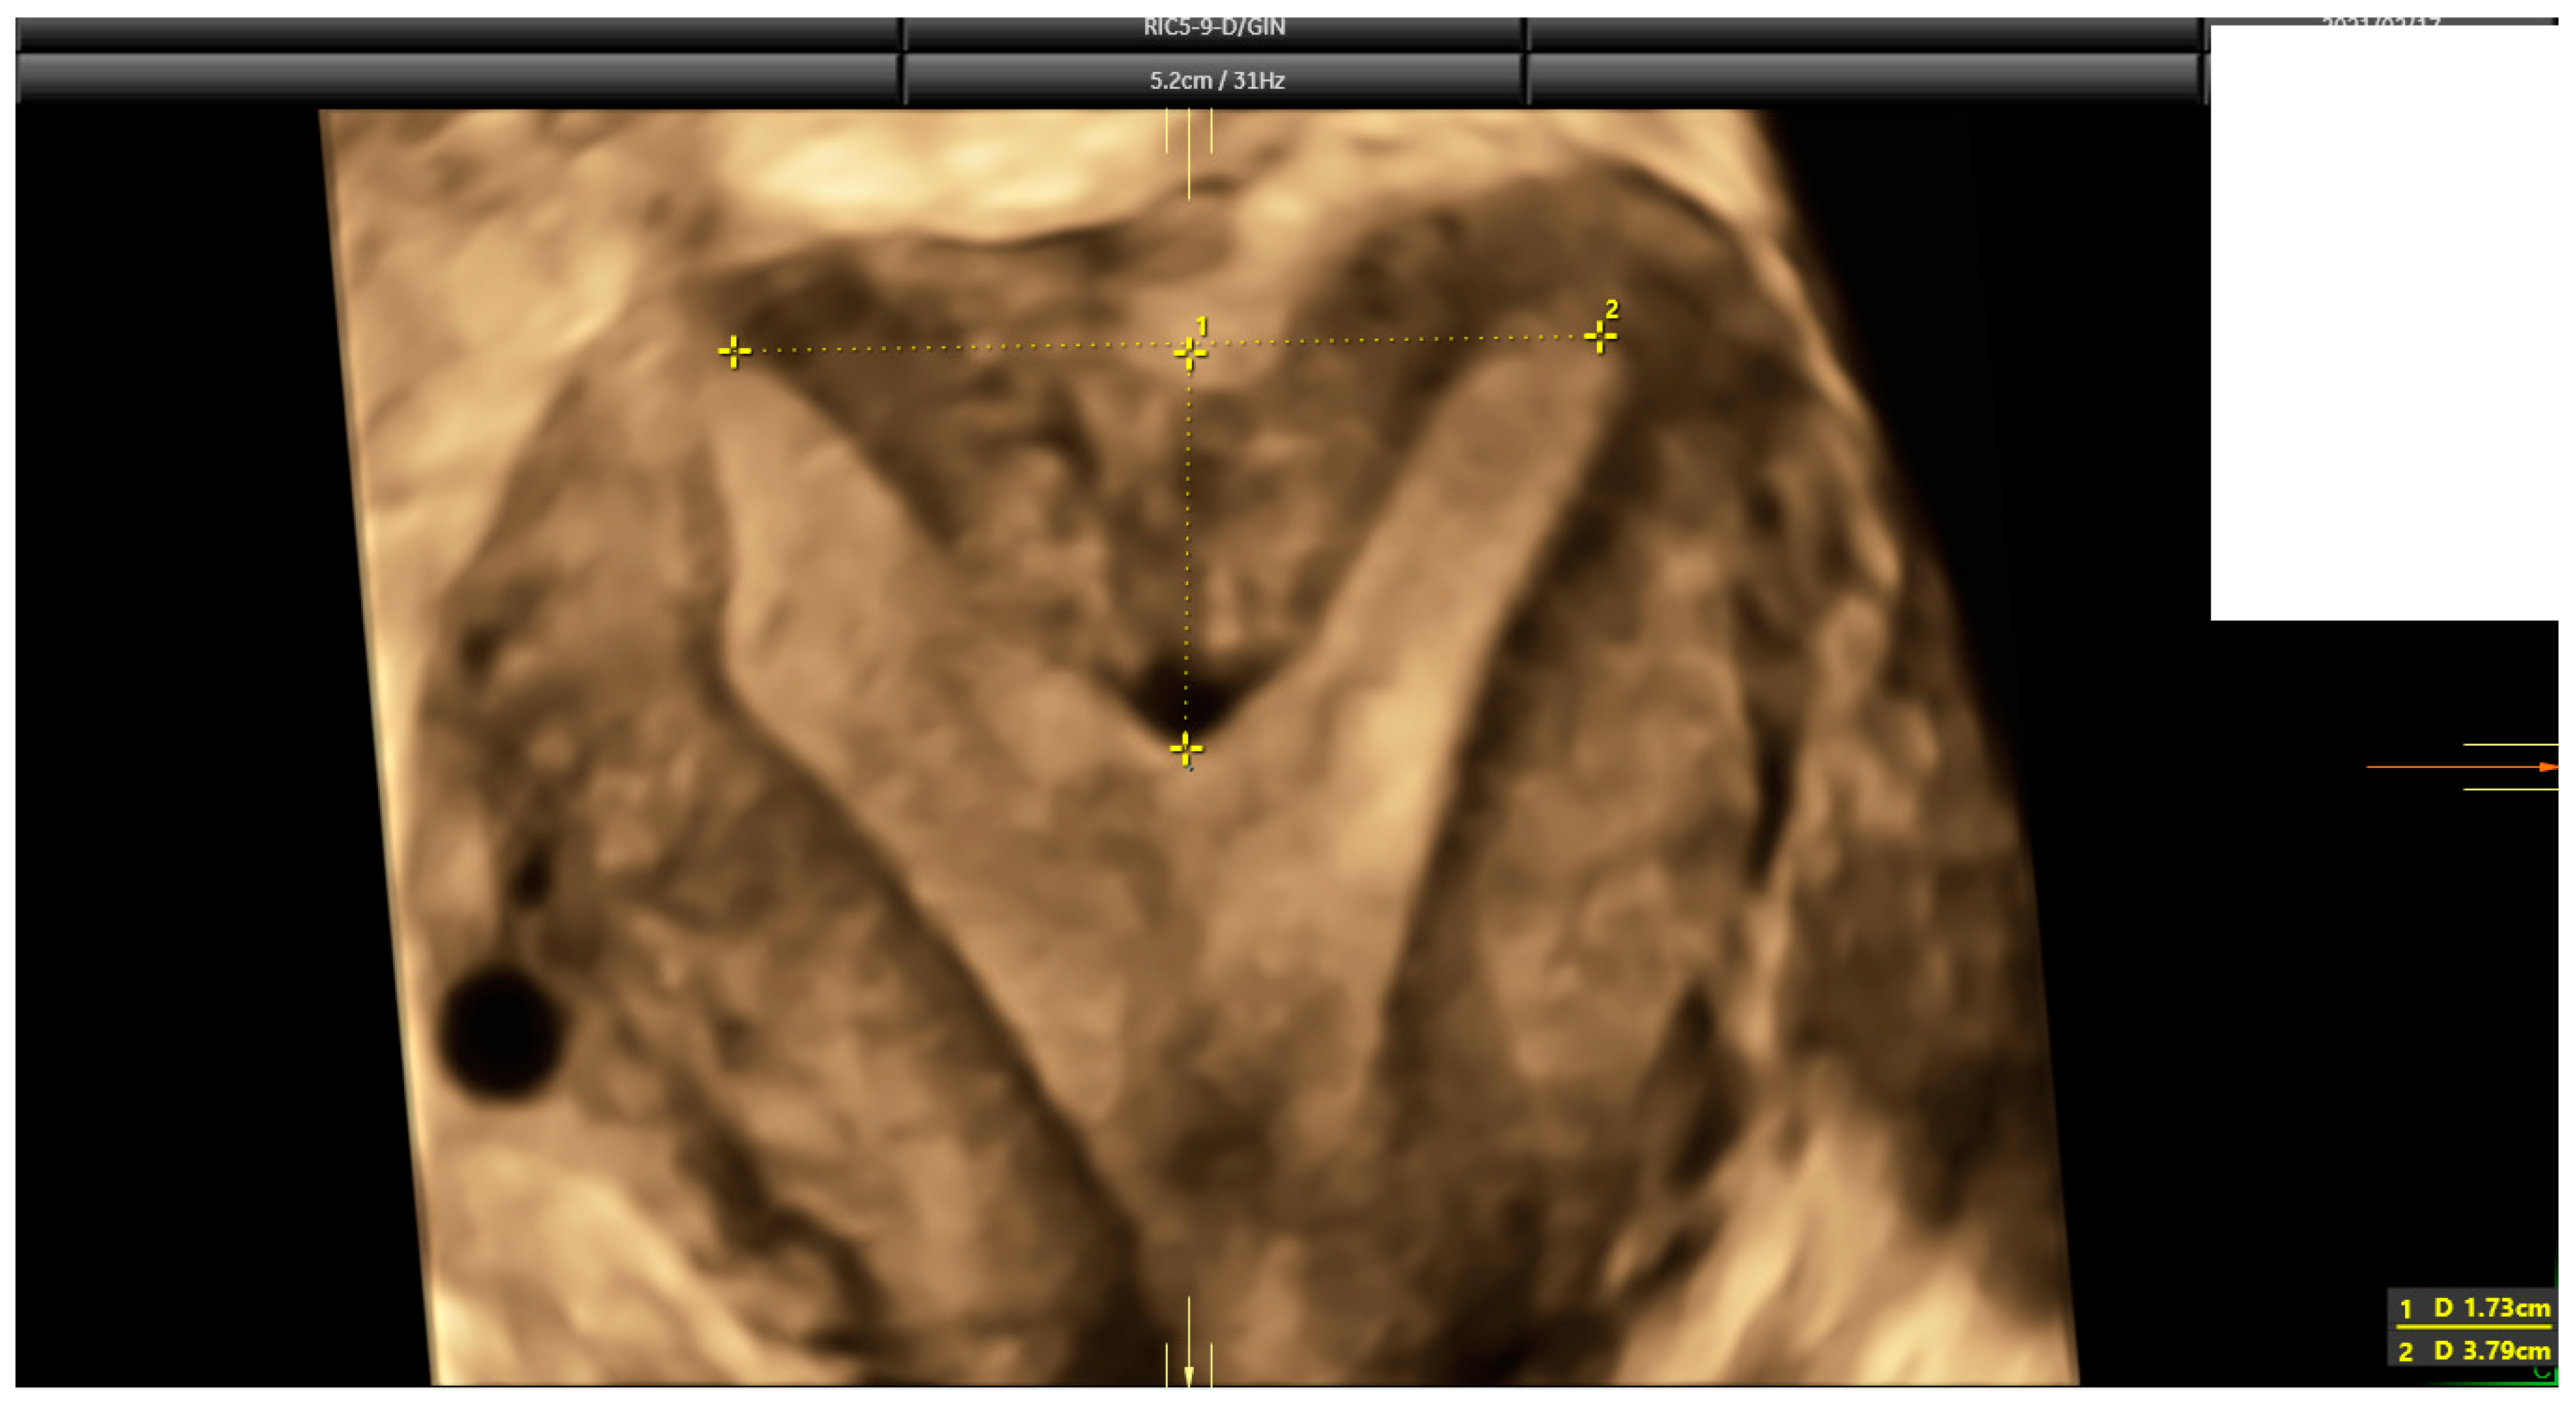

2.3. Ultrasound Evaluation

- Ludwin, A.; Martins, W.P. Correct measurements of uterine fundal internal indentation depth and angle: An important but overlooked issue for precise diagnosis of uterine anomalies. Ultrasound Obstet. Gynecol. 2021, 58, 497–499. [Google Scholar] [CrossRef] [PubMed]

| Indentation length * | 2.0 mm (2.3) | Range: 0–37 mm |

| Uterine Wall thickness * | 10.0 mm (3.7) | Range: 3.3–26.0 mm |

| Indentation angle * | 169° (21.0) | Range: 0–180° |

| I:WT ratio * | 20% (27.0) | Range: 1–596% |